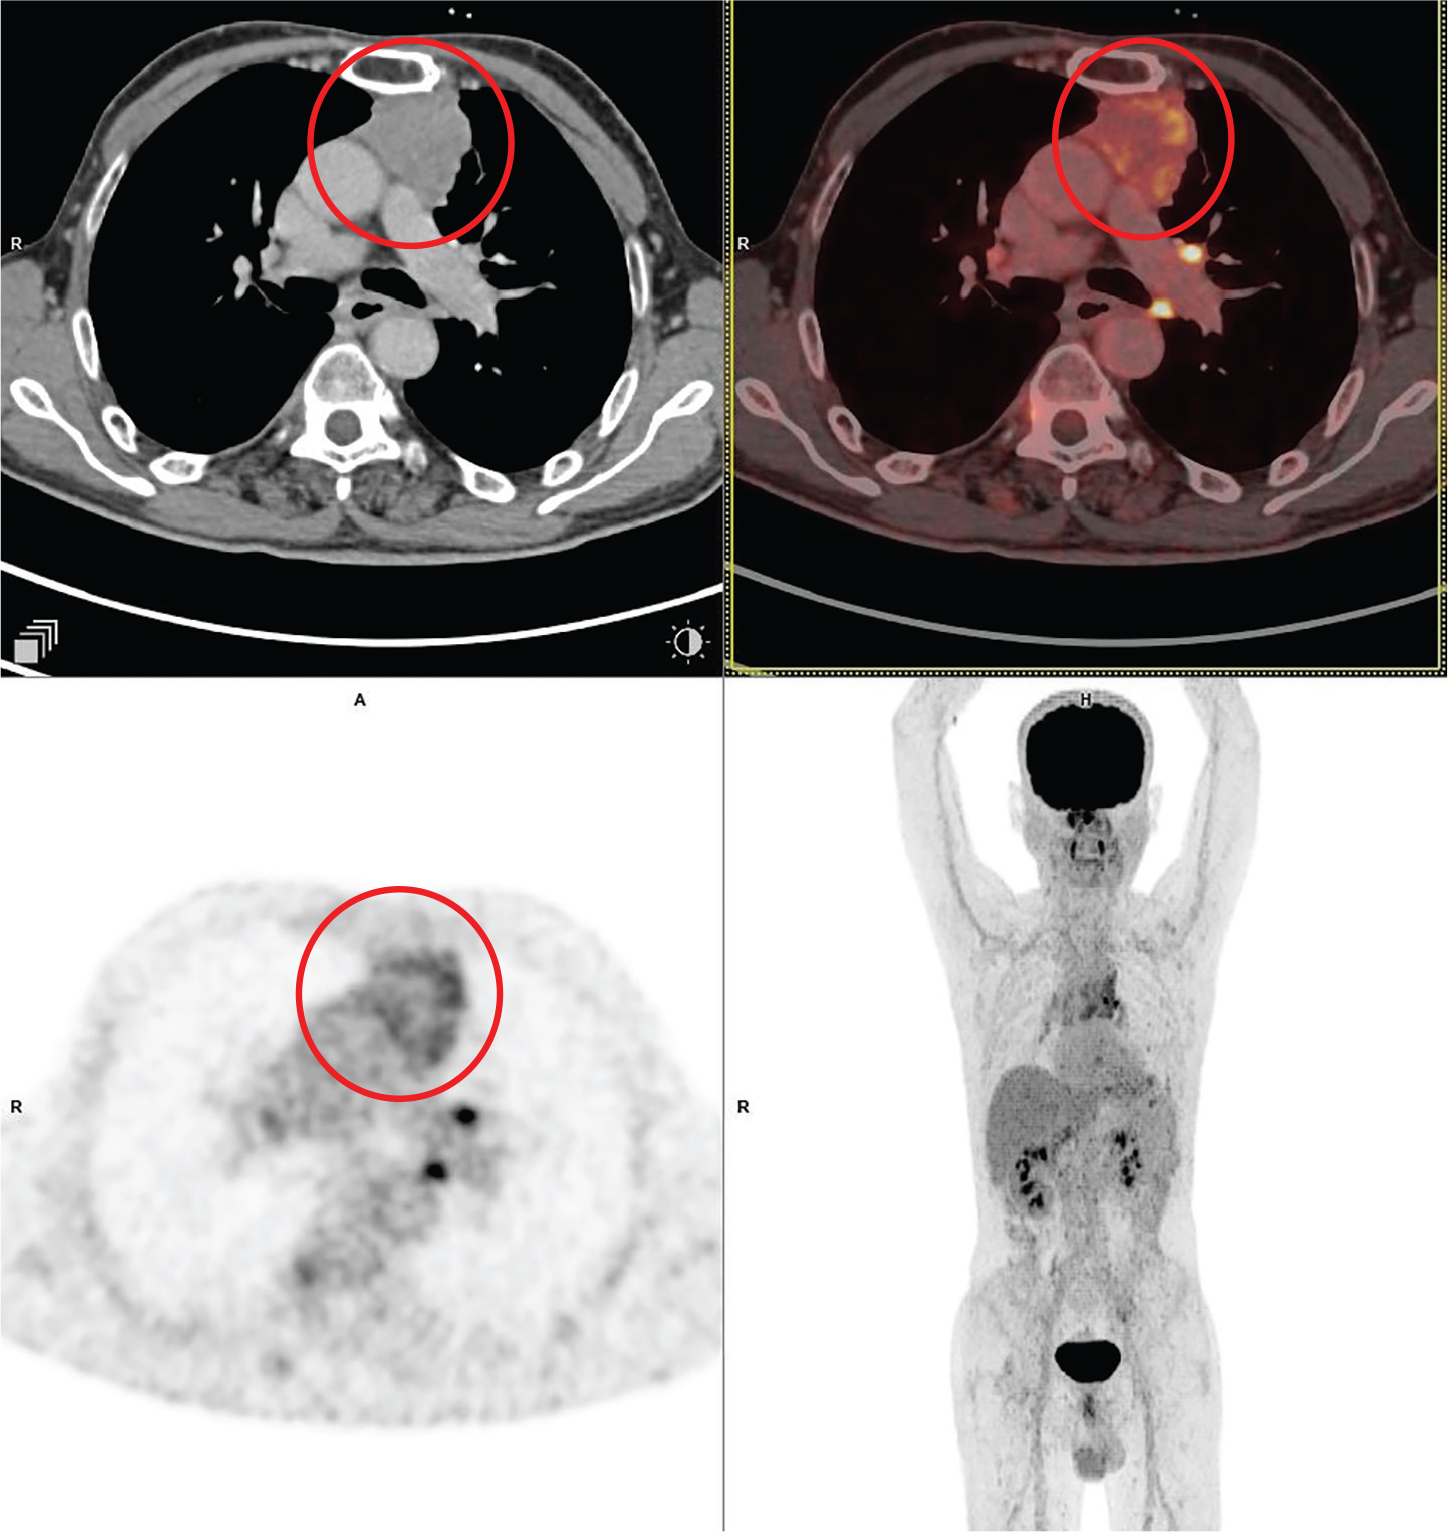

Mediastinal seminomas account for ~ 70% of extragonadal germ cell tumors in the adult population (38). On CT, mediastinal seminomas usually appear as large, homogeneous lobular masses with mild contrast enhancement. Sometimes they might have cystic, hemorrhagic, or necrotic components as seen in Figure 3. Residual mediastinal mass may persist after chemotherapy, and 18F-FDG PET/CT has been used to detect untreated viable disease. In masses greater than 3 cm, Becherer et al. (39) noticed that PET predicted residual viable tumor with a sensitivity of 80% and a specificity of 100%, compared to 73% for CT. Although specificity was much lower at 47% in another multicenter trial, sensitivity was still very high (40).

Fig 3

Figure 3. Seminoma. Anterior mediastinal mass that was pathologically confirmed as seminoma. FDG PET/CT images include axial CT (top left panel), fused axial PET/CT (top right panel), axial PET (bottom left panel), and maximum intensity projection (MIP) PET image (bottom right panel). In the red circle, a well-defined heterogeneously FDG avid and mildly enhancing lobulated soft tissue mass is seen in the anterior mediastinum on left side of midline. Non FDG avid non enhancing hypodense area seen within the mass representing necrotic component. The mass encases the arch of aorta.